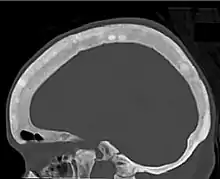

Ground glass density of the skull.[18]

CT shows focal areas of osteosclerosis.[18]